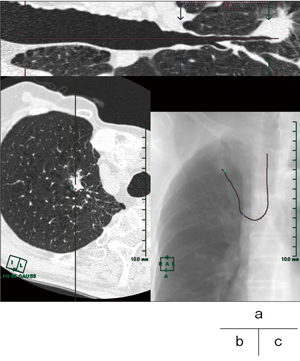

図4 CPR

a:ストレッチCPR

b:CPR直交断面

c:レイサム画像

検査施行時,透視画像でしか確認できない現状では,鉗子などを挿入している気管支を正確に判断することが困難であることも多い。透視画像は二次元のデータであり,奥行きの情報を持たない。患者のlateral方向の情報がほしいときには,管球が回転するタイプの透視装置でなければ,気管支鏡を挿入されている患者自身に体位を変えてもらうしかないが,それは大変な困難を伴うことが多い。

CPRでは,作成したパスラインに沿った直交断面を表示することができる。図4 bは,検査に適していると特定した気管支に直交した断面のCT画像である。気管支鏡のシミュレーションを想定して走行を反転して観察すると,気管分岐部から病変まで気管支が分岐していく様子を追うことができる。このとき,パスを引いた気管支は十字でプロットされており,レイサム画像(図4 c)がナビゲーションとなる。しかし,この直交断面は検査医師にとって見慣れない画像であるため,直感的に受け入れられる情報とは言い難い。